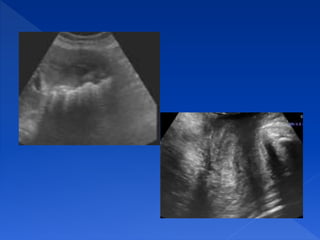

La imagen ecográfica muestra

una zona oscura detrás de una

estructura hiperecogénica.

Es una interfase muy reflexiva y

casi toda la energía del haz

sónico incidente sobre ellas se

reflejará.

SOMBRA ACÚSTICA POSTERIOR

Zonas sin ecos que aparecen

detrás de estructuras que reflejan

todos los ultrasonidos

REFUERZO ACÚSTICO POSTERIOR

Aumento en la amplitud de los ecos que se

generan tras atravesar una estructura

anecoica.

La imagen ecográfica muestra una

estructura anecoica e inmediatamente

detrás de esta aparece una zona

hiperecogénica.

Se da detrás de estructuras que contienen

líquido. Ejemplo fisiológico: la vesícula

biliar, un vaso. Ejemplo patológico: un

quiste, un derrame